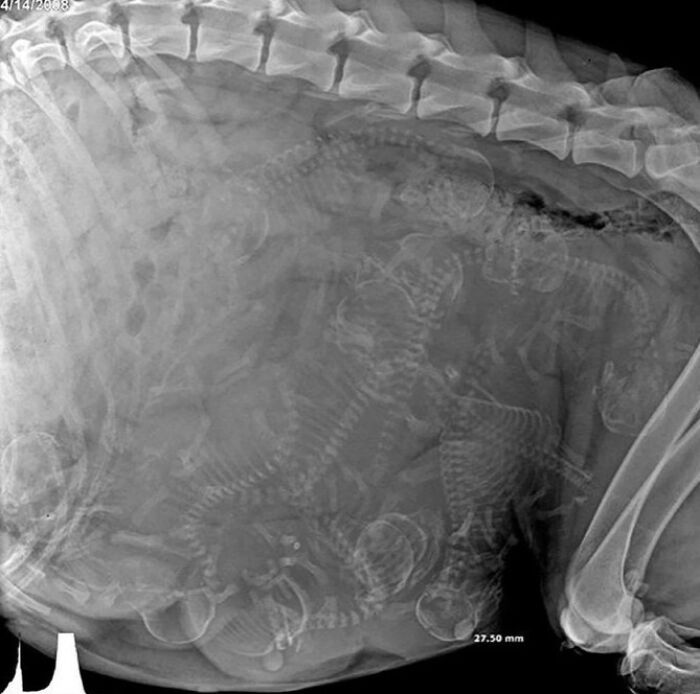

Röntgenový snímok zobrazujúci tehotenstvo psa